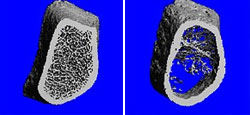

Knochenpräparate

Links: Normale Knochenbälkchenstruktur.

Rechts: Osteoporose, die roten Pfeile zeigen ein abgebrochenes Knochenbälkchen.

Feinschnitt-Computertomogramm als Querschnitt durch einen Unterarmknochen

Links: Normalbefund.

Rechts: Osteoporose, die verminderten Knochentrabekel sind deutlich zu erkennen.

(mit freundlicher Genehmigung von www.osteoporosezentrum-hamburg.de)